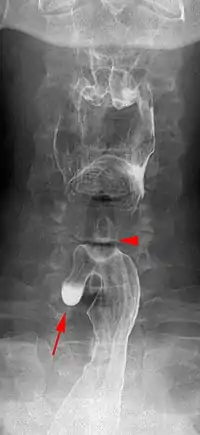

Killian–Jamieson diverticulum. Arrowhead points at the closed upper esophageal sphincter, arrow points at the diverticulum partly filled with contrast medium.

A Killian–Jamieson diverticulum is an outpouching of the esophagus just below the upper esophageal sphincter.[1]

The physicians that first discovered the diverticulum were Gustav Killian and James Jamieson. Diverticula are seldom larger than 1.5 cm, and are less frequent than the similar Zenker's diverticula. As opposed to a Zenker's, which is typically a posterior and inferior outpouching from the esophagus, a Killian–Jamieson diverticulum is typically an anterolateral outpouching at the level of the C5-C6 vertebral bodies, due to a congenital weakness in the cervical esophagus just below the cricopharyngeal muscle. It is usually smaller in size than a Zenker's diverticulum, and typically asymptomatic.[2] Although congenital, it is more commonly seen in elderly patients.[3]